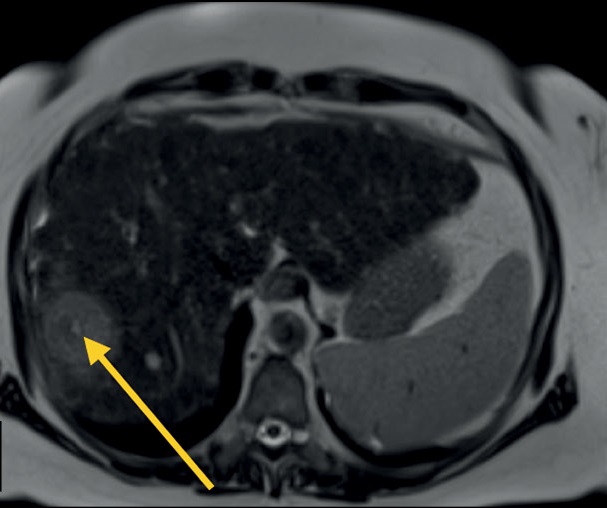

Магнитно-резонансная томография является одним из основных методов диагностики заболеваний органов брюшной полости и забрюшинного пространства, который позволяет с высокой диагностической точностью и воспроизводимостью визуализировать очаговые или диффузные изменения паренхиматозных и полых органов. Магнитно-резонансная томография имеет определённые преимущества перед компьютерной томографией в чувствительности и специфичности определения патологических изменений паренхиматозных органов, желчевыводящих путей и протоков поджелудочной железы, брюшины и органов забрюшинного пространства.

Мультипараметрический протокол сканирования предоставляет информацию не только о взаимной топографии органов и их структуре, но и о функциональном состоянии тканей, что позволяет перейти от структурной к функциональной оценке изображений. В большинстве случаев стандартный протокол включает сканирование органов брюшной полости (Т1-/Т2- и диффузионно-взвешенные режимы) и желчевыводящих протоков (магнитно-резонансная холангиопанкреатография), при этом данный протокол может быть значительно сокращён или дополнен в зависимости от целей исследования и состояния пациента.